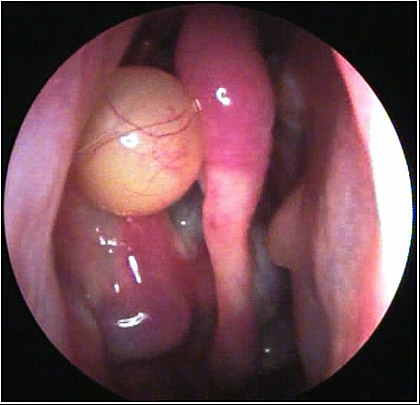

JFC Cuerpo extraño en laringe. hueso de pavo.